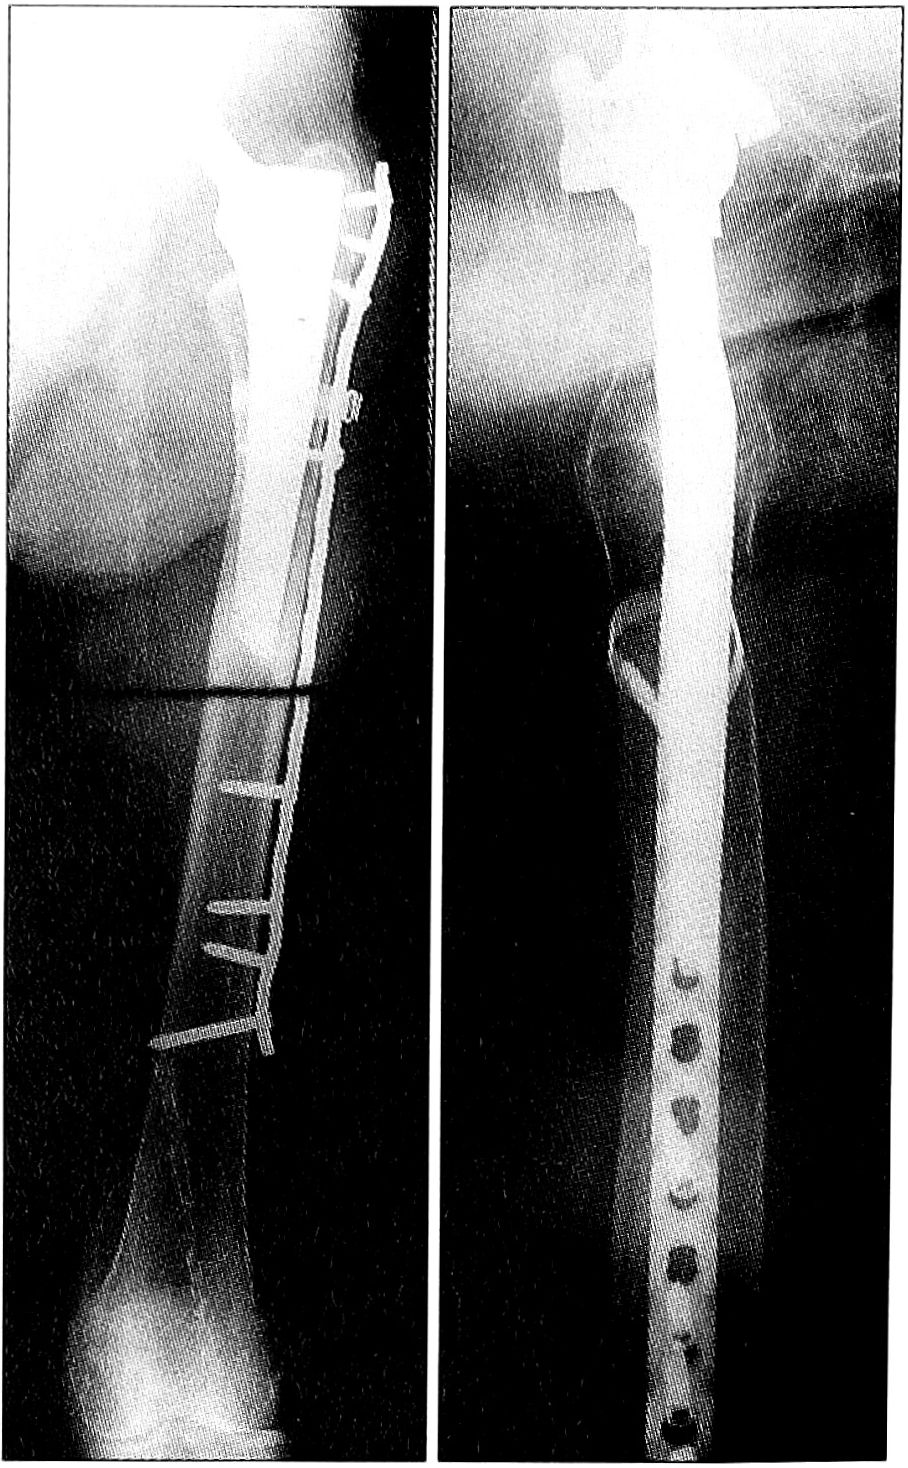

- В случае использования блокирующихся винтов хирург не должен полагаться на свои ощущения при затягивании винтов. Необходим рентгеноскопический контроль за правильным расположением пластины на поверхности кости, чтобы исключить введение винтов мимо кости (рис. 7).

Рис. 7. Точное расположение пластины является обязательным для предотвращения некорректного введения винтов (стрелка), поскольку при затягивании винтов всегда сложно определить необходимые для этого усилия.